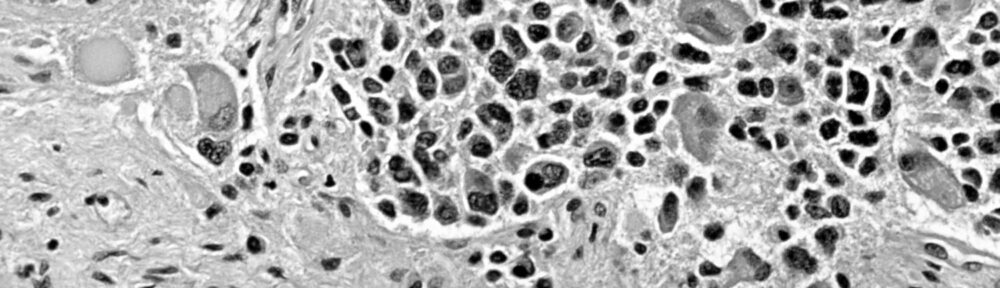

Basta. Non serve altro. In futuro, quando ti capiterà di dover discutere dell’esistenza del Dio abramitico con qualche credente, tu di’ solo questo: «Neuroblastoma».

Lo so: ho già scritto carrettate di articoli sulla teodicea. Ci torno sopra ancora perché davvero mi sembra che quella parola da sola riassuma l’argomento in modo conclusivo.

Come dici? Troppa sintesi? Non c’è problema: espandiamo e formalizziamo la «prova oncologica dell’inesistenza di Dio» – il Dio abramitico, beninteso –, come l’ha felicemente definita un mio follower qualche tempo fa.